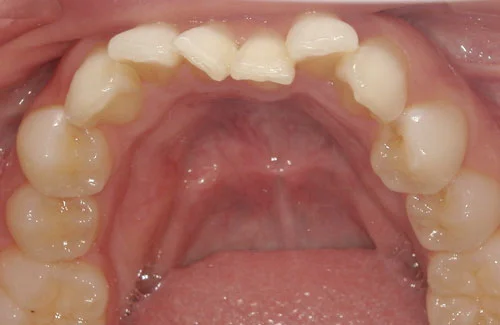

<症例3>前歯のクロスバイトでお悩み

右上の前歯2本が反対に咬合している、いわゆるクロスバイトが主訴でご来院なさいました。

主訴以外の部分には大きな叢生はなく、また患者様も装着時間をしっかり守ってくださったので約6ヶ月で改善することができました。

患者様と症状

主訴:上の前歯が出ている

性別・年齢:20代女性

問題点:上顎左側側切歯のクロスバイト、叢生

診断:前歯部の叢生を伴うアングルⅠ級の不正咬合

主なリスク:矯正中一時的に咬合しにくくなる、歯肉退縮

症状:叢生(そうせい) 上顎前突(じょうがくぜんとつ)

治療内容

治療期間:6ヶ月

治療費用:495,000円(税込)

プラン:14枚コース/ライトプラン

抜歯:親知らずのみ抜歯

再診治療費:無し

追加治療費:無し

保定装置費:無し

治療前後の写真

・2本の前歯が前突しておりましたが、矯正で自然な歯並びになりました。

・前歯の1本が下の歯の裏側に噛み合うクロスバイトになっていましたが、矯正で改善されました。